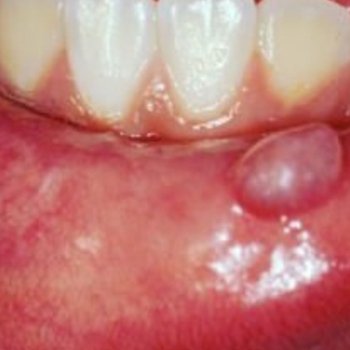

Normalmente, eles não se desenvolvem na dentição decídua, ou seja, não se manifestam nos dentes de leite da criança, aparecendo apenas com a formação da arcada permanente. Isso significa que sua formação ocorre entre os 6 ou 7 anos de idade. Na maioria dos casos, os dentes afetados são os incisivos centrais (dentes anteriores) e os molares (dentes posteriores). Os incisivos se desenvolvem em formato que lembra uma chave de fenda. Os dentes molares também podem apresentar um formato diferenciado, contando com um formato que lembra uma amora, com várias protuberâncias irregulares.

Além disso, outra característica dos dentes de Hutchinson é o maior espaçamento entre os dentes e a presença de sulcos em seu interior.

O tratamento odontológico é geralmente voltado para a estética, através de restaurações e da prevenção, com boa higienização para evitar retenção de placa bacteriana e cáries. Exames complementares como de sangue, podem confirmar o diagnóstico. E em caso positivo, a criança deve ser levada ao pediatra para tratamento adequado.